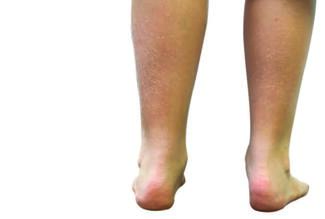

Athletic seasons may bring an influx of children with heel pain into podiatric offices. However, the sedentary results of the COVID-19 pandemic may also cause symptoms in need of evaluation. Here the author outlines appropriate history...